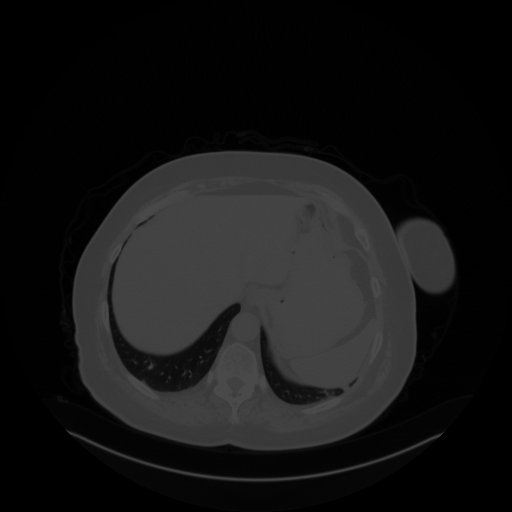

Original VENOUS CT scan

Full window (WL 1023.5, WW 4095 β†’ Low βˆ’1024, High +3071)

Lung window (WL -600, WW 1500 β†’ Low βˆ’1350, High +150)